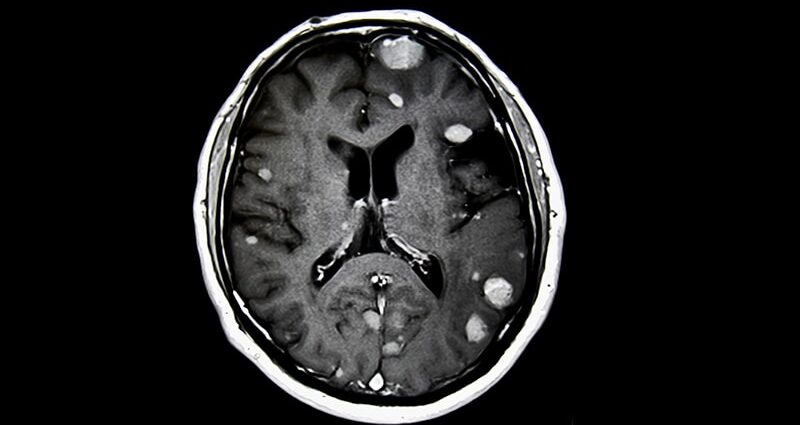

Patients undergoing stereotactic radiosurgery before resection of brain metastases demonstrated low rates of local recurrence, radionecrosis, and nodular leptomeningeal disease at 12 and 24 months, a new analysis found.

- For patients undergoing resection for brain metastases, postoperative stereotactic radiosurgery improves local control. However, radiosurgery after surgery comes with disadvantages, such as increased rates of leptomeningeal disease and radionecrosis. Providing radiation before surgery could help overcome these issues.